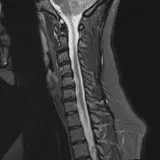

Over 2,100 interactive radiology cases, curated by radiologists for your level of training. Scroll, window, and view cases full screen — just like on PACS. Click linked findings in each writeup to jump straight to them on the image. Cases include sample reports, a focused discussion section, original illustrations, and videos.

Des cas entièrement interactifs avec les outils attendus d'un PACS — défilement, fenêtrage, zoom, déplacement, mesures, ROI et mode plein écran.

Des annotations détaillées mettent en évidence les résultats clés directement sur les cas. Cliquez sur les résultats liés dans les descriptions de cas pour accéder à leur emplacement exact sur l'examen.